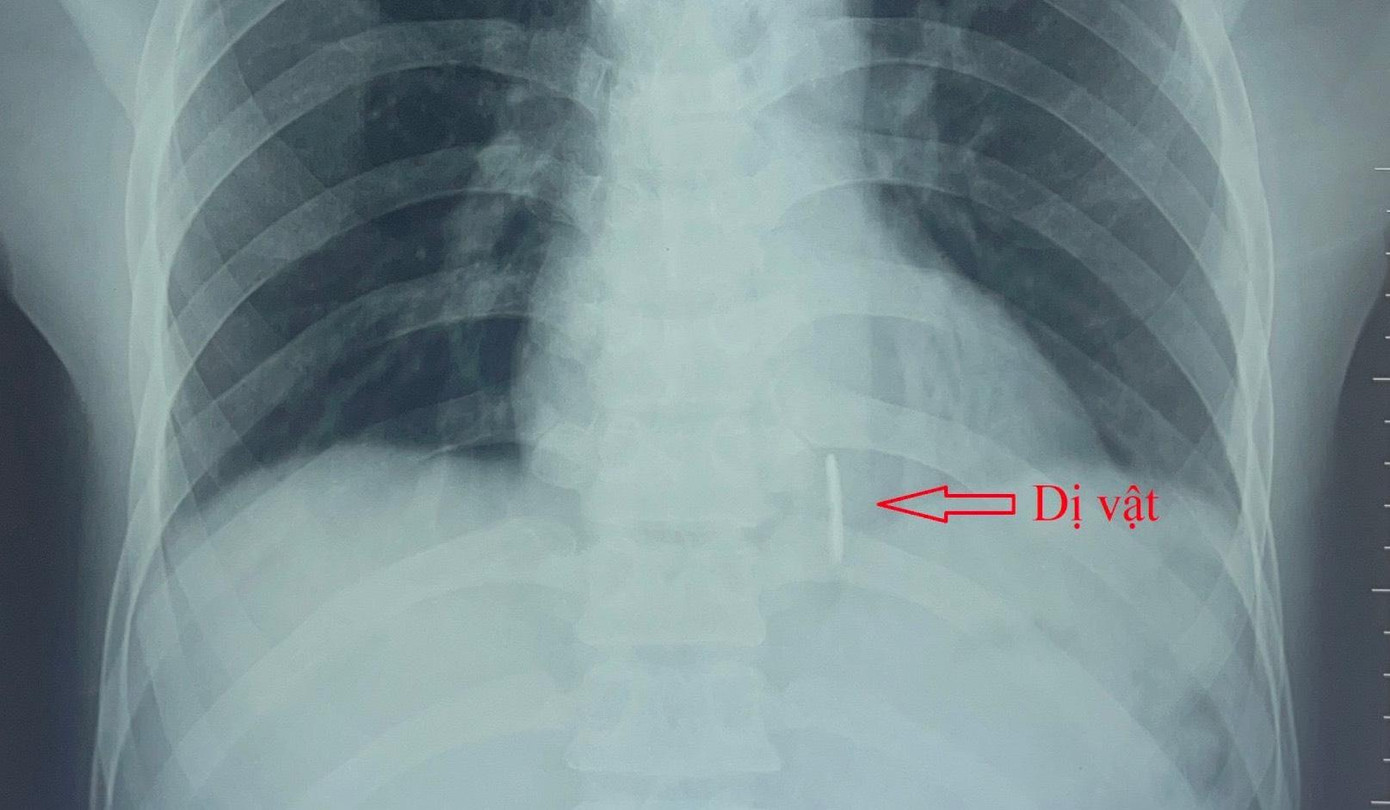

| Hình ảnh dị vật qua Xquang. |

Bệnh nhân nhập viện trong tình trạng vết thương ¼ trên bụng phải kích thước khoảng 2x5mm. Tiếp nhận, các bác sĩ nhanh chóng thăm khám và tiến hành Xquang ngực tim phổi thẳng, siêu âm tim màu, chụp cắt lớp vi tính lồng ngực có cản quang. Kết quả ghi nhận, có 1 dị vật cản quang dài 4x0.4cm nằm dọc thành sau thất trái và có thông vào buồng tim.